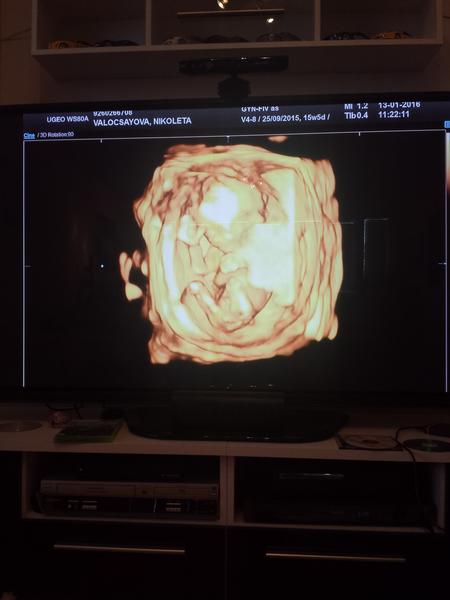

@sara34valentina @mimikas @sara22 @wewitta @agathachristie @badimeria @melisssssa babulkyyyyyy cakame na 80% malu princeznickuuuu 😵 😵 Mame 10,4cm od hlavicky po zadocek a plus nozky okolo 5-6cm 🙂 Pekne sme sa hybali robili akrobacie cmulali si prstek natahovali sa a malinka dokonca aj zamavala mamicke 🙂 🙂 Tesiiim sa velmiii 🙂

@nicolettka2126 jeeejo,gratulujem,baby su super 🙂

A mas aj fotecky? Videla si aj ty kavove zrnko,ci este nebolo tak identifikovatelne?

@nicolettka2126 jeeeeeej Gratulujem maminka ♥ takze sme sa kopli a v brusku je princeznicka ♥ mne sa predvcerom snivalo ze cakas dievcatko , lebo si kupovala kvietkovane satocky s volanikmi, ale reku pockam kym napises 😉 mojko teskam sa stebou a teraz hor sa na*nakupy* moje zlate, nech len pekne si ho cmula, a ochutnava tvoju plodovu vodicku, mas fotku?

@sara22 mam fotecky na cdcku len notebook mi to neprehra neviem preco iba dvd prehravac a su tam aj videjka no tie mi nespusti neviem aky program to vyzaduje, musim sa popytat draheho bratranca ten je expeet na taketo veci 🙂

Veru ano ukazala mi malu pisulku, este tam bol sice malinky vybezok ale bolo to jasne ze to nie je pipik 🙂

@nicolettka2126 tak skus cez dvd dat na tv a odotit mobilom ale to asi nebude zaostrene ze? juj skus daco vymysliet, tesim sa na fotecku 🙂ako sa citis?

@sara34valentina ano ano mam fotecky len musim nejaky speci program stiahnut asi lebo na cdcku to mam vsetko 🙂 Pohram sa s tym a potom hned pridam 🙂

Jeeej tak si tusilaaaa 🙂 Supeeer 🙂 Joj taka bola nadherna, aktivna vkise nieco robila moj maly pokladik 🙂 Veru takze hooorsa na ruzove vecickyyyyyy 🙂

@sara34valentina ano ani skusim tak a potom s aporadim s tym draheho bratrancom 🙂 On isto nieco vyspekuluje 🙂

@nicolettka2126 uplne poznam ten pocit. ked este necitis pohyby tak kazde sono je ten najkrajsi okamih na svete 🙂 vzdy som odchadzala ako na oblaciku stastia. vychutnaj si to, je to vas den 🙂

@agathachristie veru ano prekrasny pocit taka hrdost obrovska a stastie neopisatelne 🙂

@nicolettka2126 jeeej moja 🙂 super 🙂 sice furt som k tebe spajala chlapca 🙂 ruzova je super 🙂 aj ja chceeem 🙂 a tesiiim sa na foteckyy 🙂

A morfo mam nasledujucu poradnu u svojej dr to budem 19+4 🙂